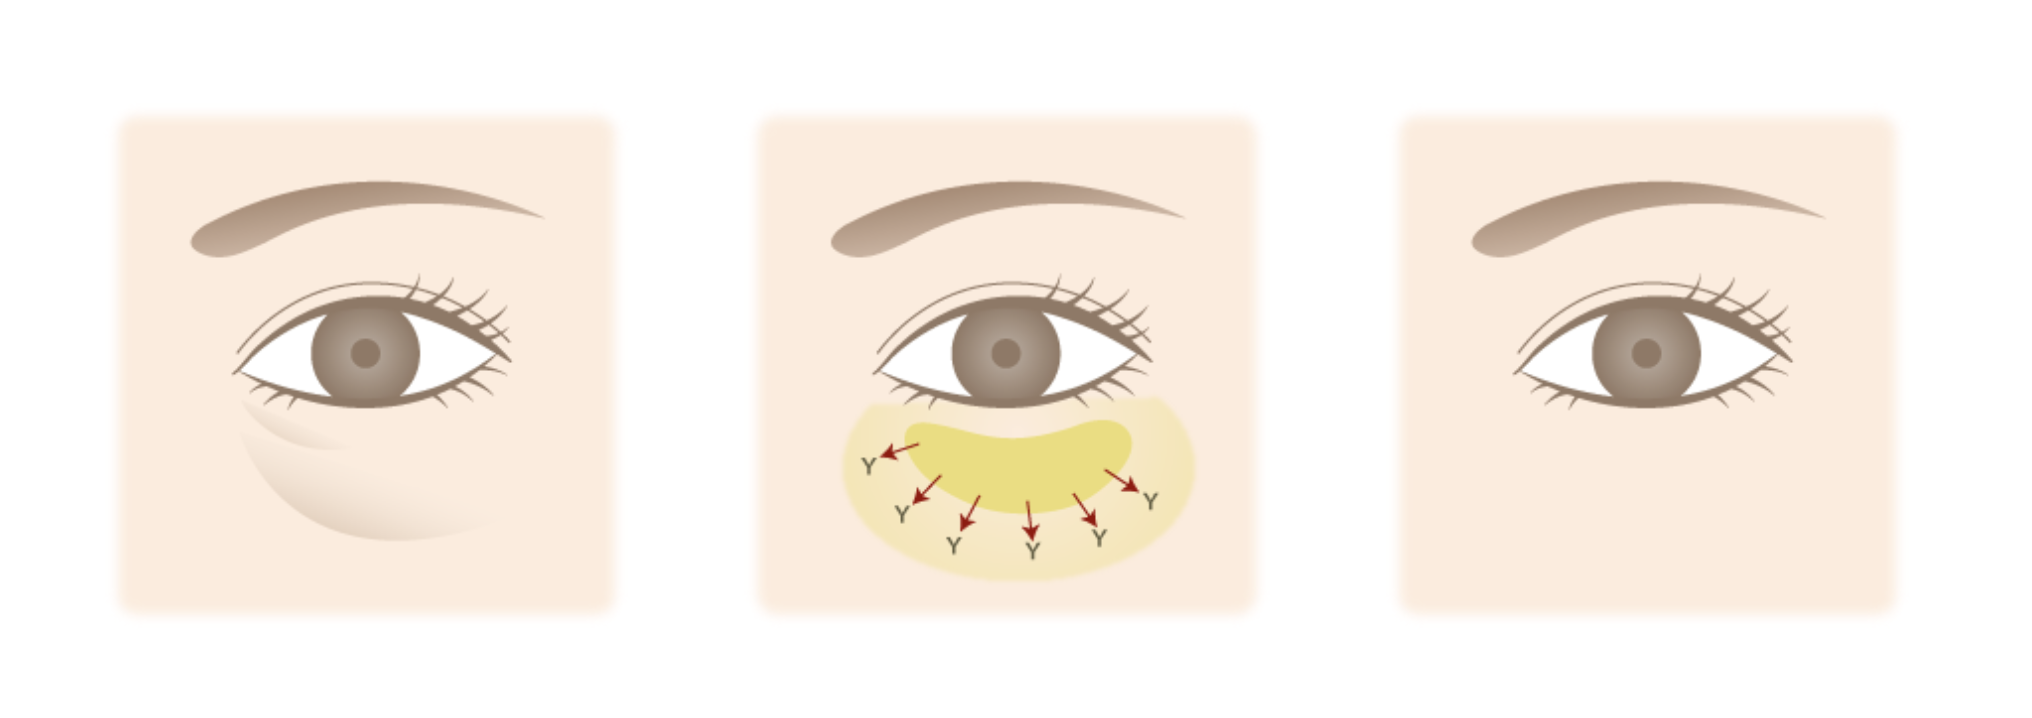

Aboutハムラ法

『ハムラ法(目の下のたるみ取り)』は、飛び出した眼窩脂肪を切除せず、ボリュームが減少した目の下のくぼみへ脂肪を移動させる治療法です。1回の施術で「眼窩脂肪の突出」「皮下脂肪の減少」を同時に解消し、目元の凹凸をフラットにすることができます。しかもヒアルロン酸などの薬剤を入れることがないので、仕上がりがナチュラルで、持続性が高いのも魅力です。

Lower blepharoplastyハムラの特徴

Features 01

皮膚のたるみと脂肪のふくらみを同時に整える

まぶたの外側を切開することで、余分な皮膚の除去と脂肪の再配置が可能です。たるみ・ふくらみの両方に対応できます。

Features 02

表面のシワや余剰皮膚の引き締めにも適している

皮膚のたるみが強い場合でも対応でき、下まぶた全体の若返りを目的とする方に選ばれています。

Features 03

傷跡は下まつげの際に沿って目立ちにくい工夫

切開線は自然なラインに合わせて行うため、術後はほとんど目立たなくなることが多いです(※個人差あり)。

About裏ハムラ法

「裏ハムラ法」は、まぶたの裏側を切開して、脂肪を移動させる方法です。皮膚を切らないので、表面に傷跡を残さず治療が可能です。ただ『ハムラ法(目の下のたるみ取り)』と違い、皮膚のたるみを解消することは難しいので、症状によっては充分なたるみ改善効果を得られないことがあります。 当院では、一人ひとりの症状を見極め、「ハムラ法」「裏ハムラ法」のどちらが最適かをご提案しますので、たるみ症状や自身にぴったりの治療法が分からなくても、安心してご相談ください。